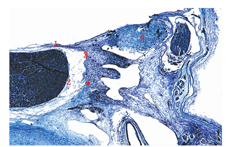

垂体囊在垂体的两侧,即海绵窦内侧所在部位,构成海绵窦内侧壁的外层,连同海绵窦内的膜状纤维结缔组织构成海绵窦内侧壁的双层膜性结构[11](图1)。而海绵窦内侧壁有时存在缺损,可能是垂体腺瘤容易累及海绵窦的因素之一(图2)。